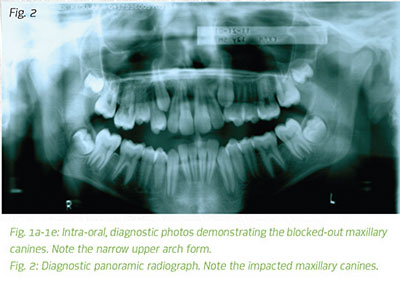

A 12-year-old male presents in my office for an orthodontic evaluation. He has Class I malocclusion with completely blocked out maxillary canines and moderate to severe crowding in the lower arch. At first take, a four-bicuspid extraction treatment plan would appear to be appropriate. However, in my practice, I always take complete diagnostic records, including lateral, frontal, panoramic and hand-wrist radiographs on all my patients before committing to a particular treatment plan. These radiographs for each patient are always sent to Rocky Mountain Orthodontics Data Services for cephalometric tracing and analysis. The information I receive includes a Ricketts analysis of the lateral and frontal head films, a Ricketts forecast for dento-facial growth and visual norms for both the lateral and frontal analyses.

The maxillo-mandibular relationship two years after the start of treatment in an adolescent might not be the same at maturity. When growth is not taken into account, an orthodontic case treated to proper balance at age 12 can become a failed result at maturity. This is especially true in cases that are predicted to experience a large amount of mandibular growth during their teens. A decision was made to use rapid maxillary expansion followed by upper and lower fixed appliances to resolve this patient's crowding issues. The maxillary canines erupted into proper position producing this functional and aesthetic result.